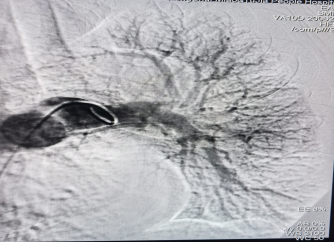

第二,开展新技术新业务,填补彭水县的医疗领域的空白。与彭水血管外科团队通力合作,先后开展了主动脉夹层腔内隔绝术,肺动脉造影吸栓术各1例,手术效果良好,患者均已康复出院,回访患者恢复良好。

典型病例资料2: